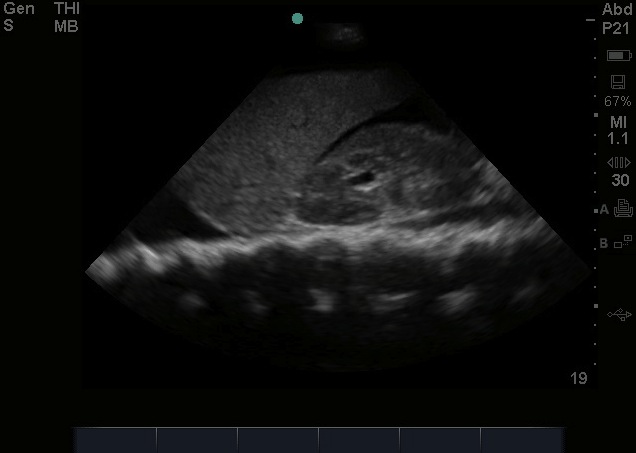

Theoretically, given its dependent anatomical position, one might logically conclude that it should in fact be the most sensitive view to visualize free fluid; unfortunately, the literature has negated this theory – and in fact this can often be the least sensitive view, largely in part of human error, and especially in pelvic fractures.(1,2,4) Anatomically, when we scan the suprapubic area in both transverse and longitudinal planes, there’s a lot that we see –the bladder, bowel, pelvic bones, pelvic organs, and rectum to name a few. This might make it harder for us to visualize free fluid, and separate it out from these other structures. But here’s a few tips to help overcome these limitations. Begin by placing your phased array or curvilinear probe just above the pubic symphysis, aiming inferiorly/caudad into the pelvis.

1. Look through a full bladder. A full bladder – The suprapubic view is visualized using a filled bladder as the acoustic window. Not all trauma patients come in with a full bladder and we will not likely go back to the days when a foley catheter used to be placed in order to fill the bladder for visualization. While we are sure our patients appreciate us not doing this anymore – its important to note, that if your patient has an empty bladder, it is best to hydrate them up with the fluids, and repeat the scan when the bladder is more full.(5) With an empty bladder your ability to adequately discern free fluid is very limited. Mostly due to gas scatter from bowel, inadequate depth adjustments, and inability to discern bowel fluid from free fluid. Click Here for a Video of A Normal Female.

2. Adjust your depth – More often than not, when it is time to scan the suprapubic area, your depth is set too deep from scanning the upper quadrants or cardiac views. We often find that a depth of about 13cm to 16cm optimizes your view. The goal is to have your bladder centered on the screen, to easily visualize the areas surrounding the bladder

3. Adjust your gain – The bladder is a fluid filled structure, and as mentioned before, fluid is the “lover” of ultrasound, allowing structures deep to it to be well visualized, however this often creates an artifact called “posterior acoustic enhancement” that produces a hyperechoic and bright area deep to the bladder. This makes it hard to visualize anechoic or black free fluid. One of the biggest pitfalls is not decreasing your gain to accommodate for this, and limiting your ability to pick up anechoic free fluid.

4. Look everywhere – Unlike in your upper quadrants, free fluid in the pelvic cavity can in fact collect anywhere – anterior, lateral, and posterior to the bladder as well as anterior, lateral, and posterior to the uterus in female patients. This often is dictated by your patient’s position, the lay of the uterus, how full the bladder is, and the size of the prostate to name a few. We suggest looking in four areas –

7. Fan slowly – While fanning is always important in evaluating any region by ultrasound – we cannot stress it enough when evaluating the suprapubic area. It is impressive and often surprising just how much free fluid can “hide” behind and around the many structures present in this region, and not be visualized unless you dedicatedly fan through the area. It is strongly encouraged to view the suprapubic area in 2 planes – horizontally and longitudinally and fan through each section slowly to make sure you don’t miss any free fluid!(3)